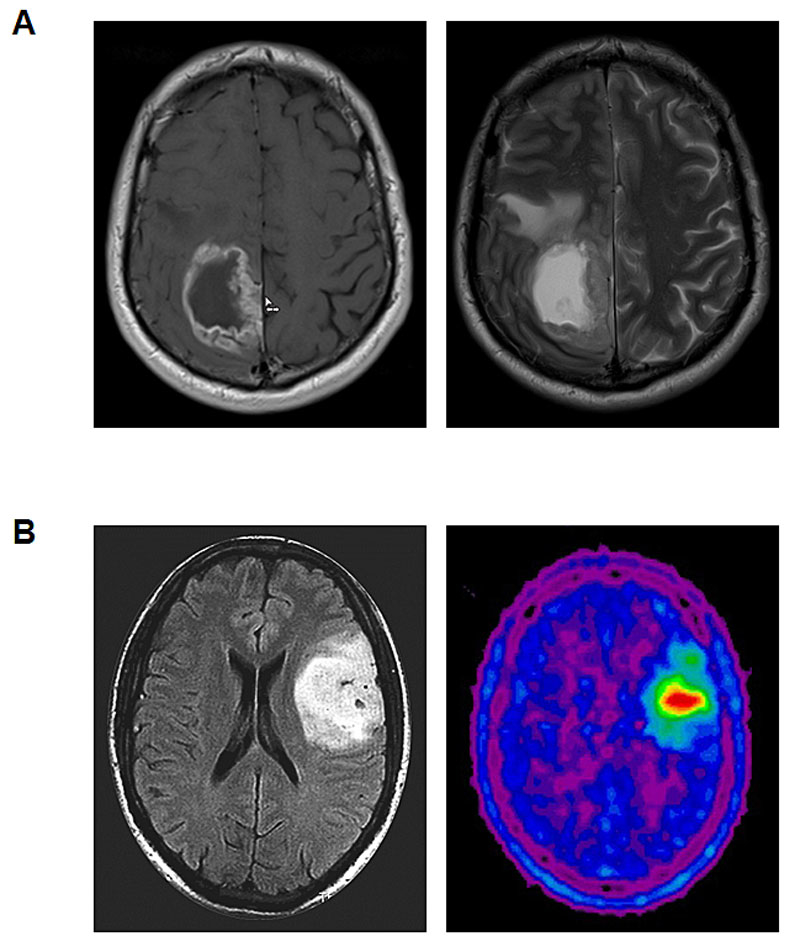

Gliomas may present with various neurological symptoms or signs, including seizures, focal deficits, cognitive alterations or any other focal neurological symptom or sign that triggers an imaging procedure. Magnetic resonance imaging (MRI) is the gold standard for the detection and monitoring of gliomas and evaluation should be according to RANO criteria [8]. Only patients who are unable to undergo MRI should be examined by computed tomography (CT). Amino acid positron emission tomography (PET) has become increasingly available and may be used in selected patients for various purposes including the delineation of tumour extension, the definition of appropriate biopsy spots in non-contrast-enhancing tumours and radiotherapy planning, as well as monitoring of tumour growth and response assessment (fig. 1) [9].

Figure 1 Representative imaging findings in glioma patients. A. Glioblastoma. T1-weighted contrast-enhanced MRI (left) and T2-weighted MRI sequence (right). B. Oligodendroglioma WHO grade 2. T2/FLAIR-weighted MRI (left) and 18F-fluoroethyl-tyrosine (FET)-PET (right).